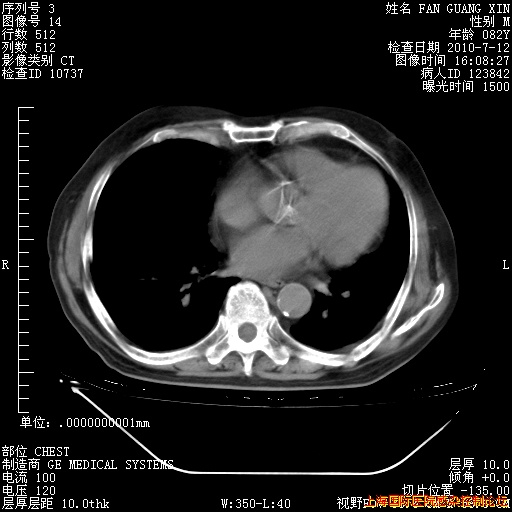

今天复查CT

今天CT

整整相隔30天的肺部CT好像有所好转啊。甲强龙减量第3天,需要观察体温。